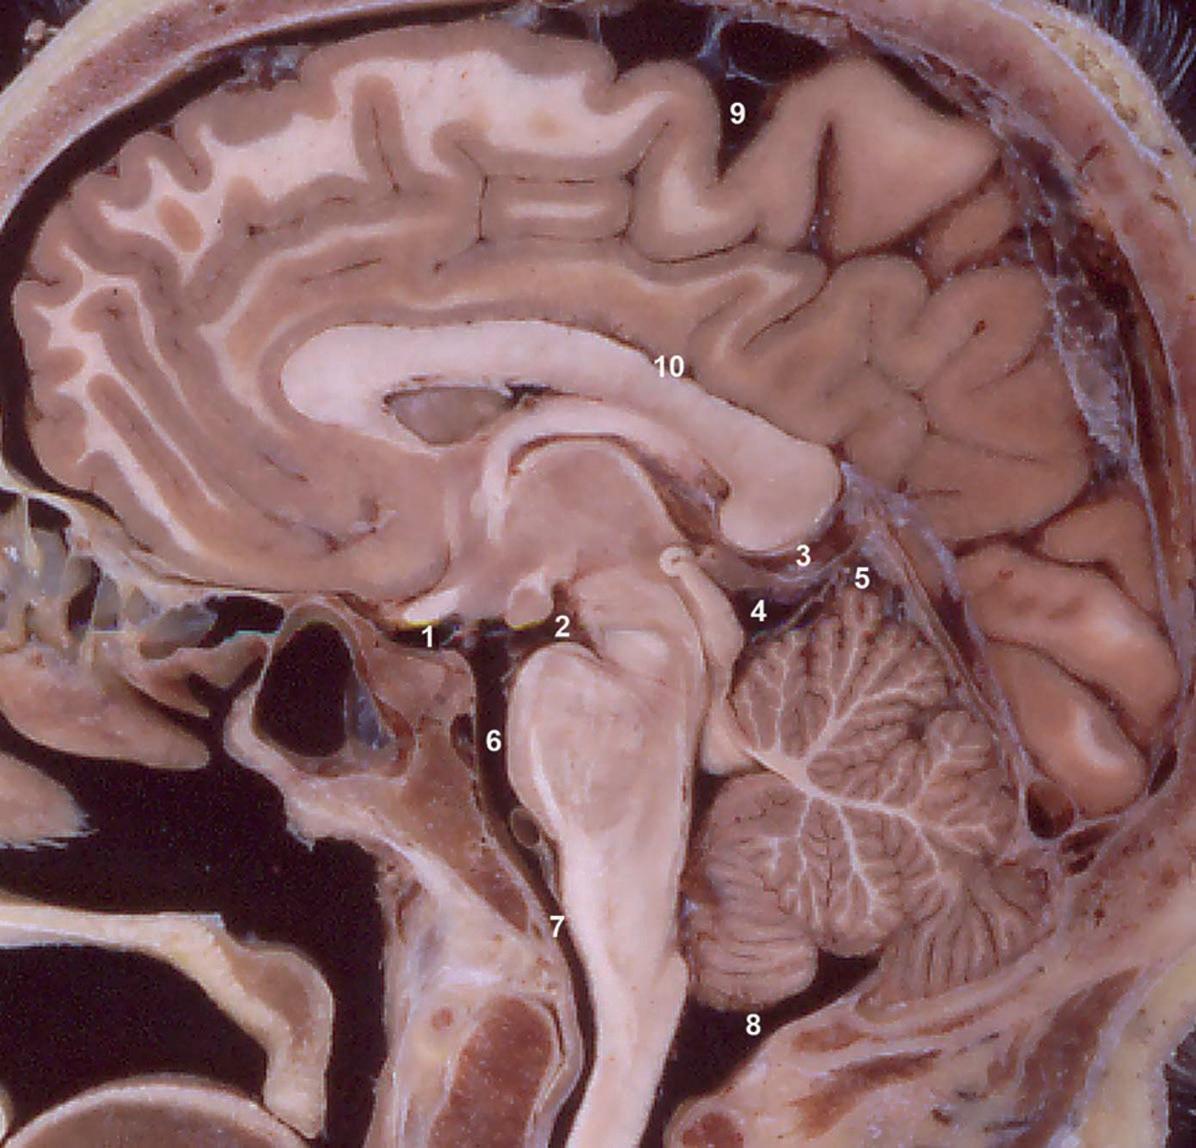

Fig. 1.16

Citernes des espaces sous-arachnoïdiens.

1 : Citerne chiasmatique. 2 : Citerne interpédonculaire. 3 : Citerne de la grande veine cérébrale. 4 : Citerne de la lame tectale. 5 : Citerne cérébelleuse supérieure. 6 : Citerne pontique. 7 : Citerne médullaire. 8 : Citerne cérébellomédullaire. 9 : Citerne du sillon central. 10 : Citerne péricalleuse.